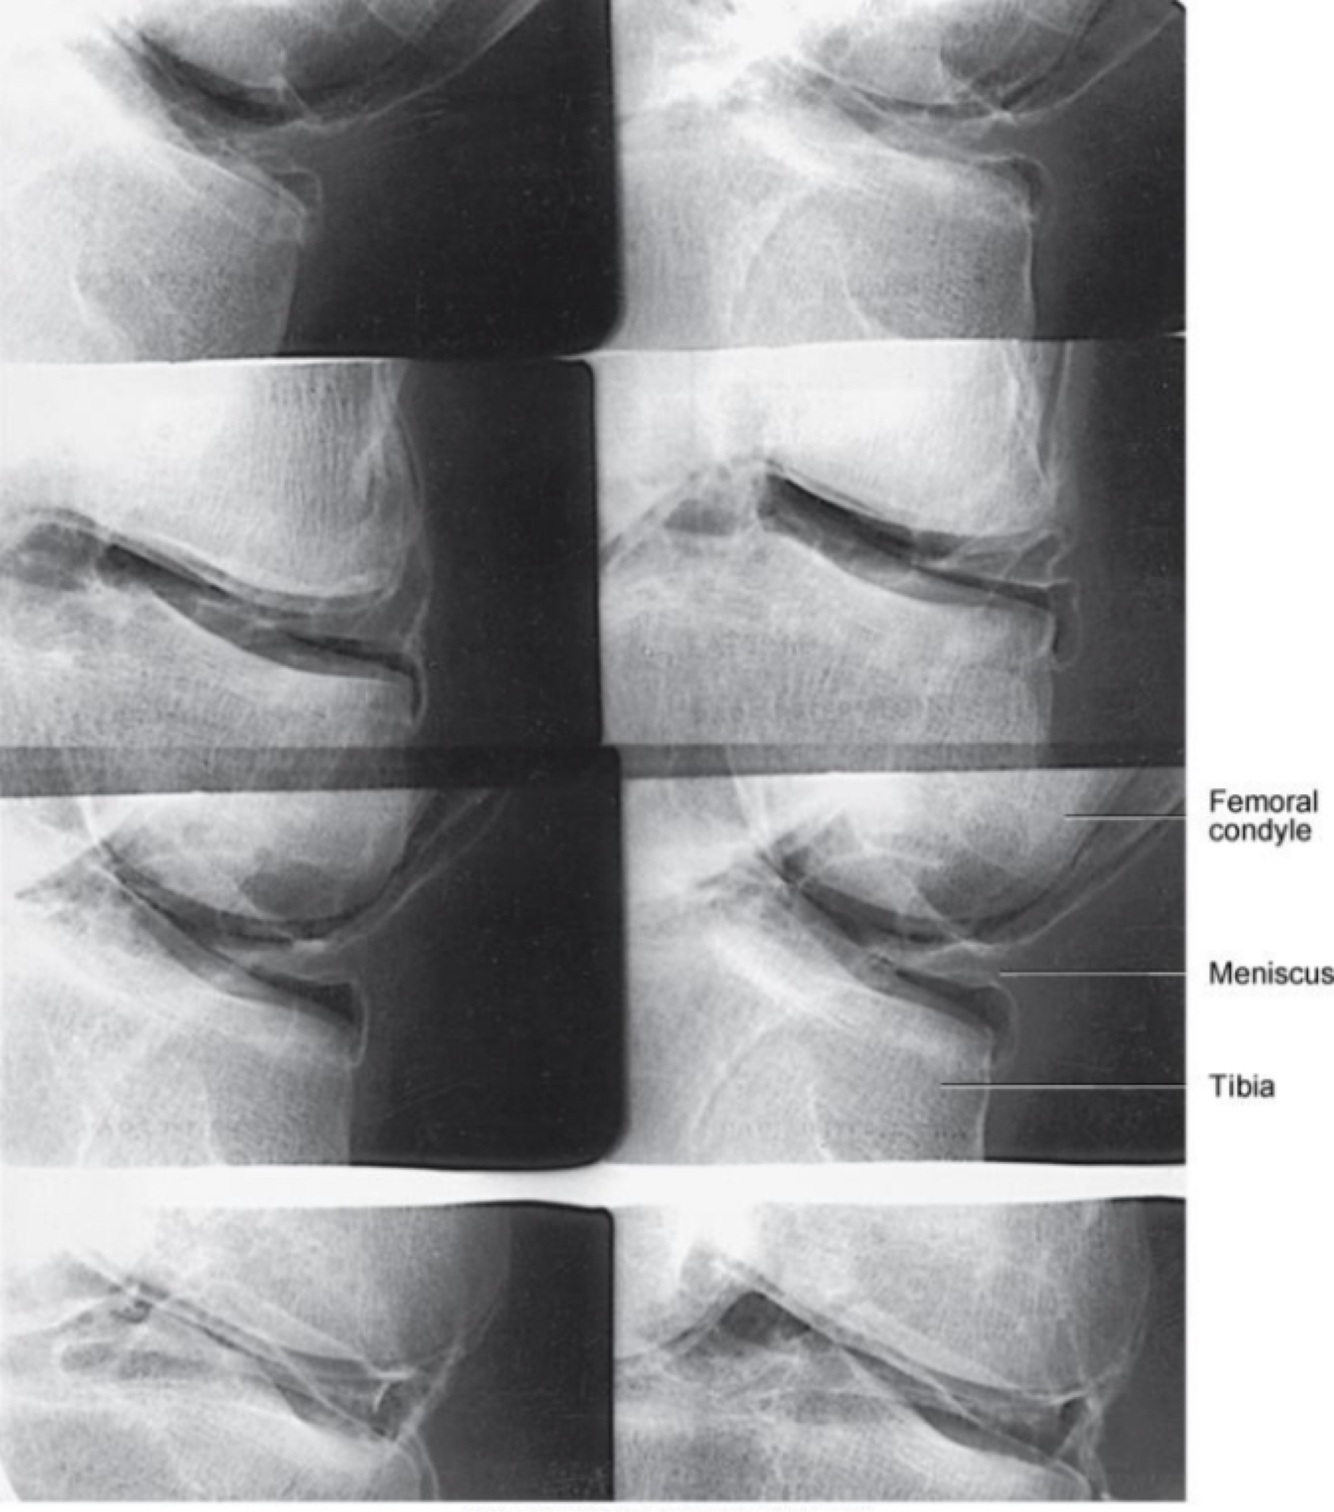

Knee Arthrogram Images

• Uses a stress device

ANATOMY OF THE KNEE

• Femur, tibia, fibula, and patella

• Held together by network of ligaments

-Posterior cruciate ligament

-Anterior cruciate ligament

-Tibial collateral ligament

-Fibular collateral ligament

• Lateral and medial menisci